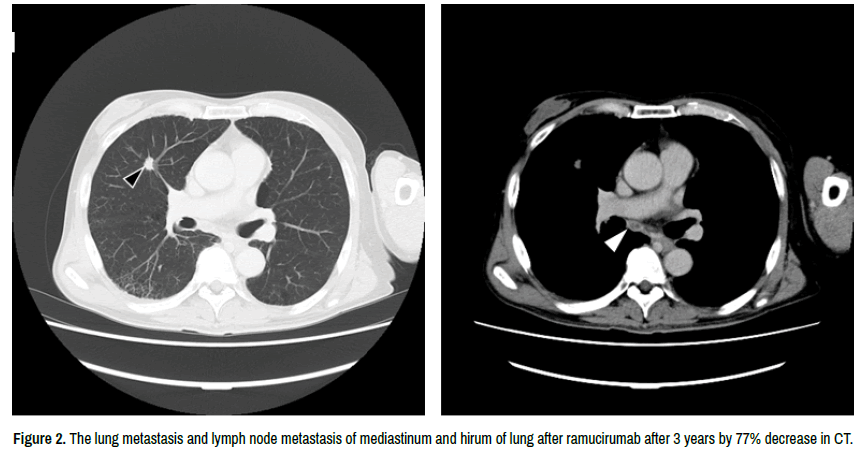

In the second-line setting, he participated in a randomized, double-blind, placebo-controlled phase III trial with ramucirumab vs. best supportive care (REACH) in December 2012. He was randomized to receive ramucirumab and the size of the tumor decreased to a partial response by 45% in first 6 weeks. His tumor decreased by 77%, with only a small fibrotic mass remaining in 36 months (Figure 2). AFP and PIVKAII also decreased to 1 ng/ml and 33 mAU/ml. His adverse effects were proteinuria Grade 2, arthralgia Grade 1, and hypoalbuminemia Grade 1 from first 6weeks. These were observed without any treatment. Unblinding was performed on 28th August 2014. He continued to receive ramucirumab, however developed hypoalbuminemia Grade 2 in December 2015; therefore, drug administration was stopped. No recurrence or progression was observed over 4 years up to December 2019. Therefore, the complete tumor response was suggested although the best overall response was Partial Response (PR) according to RECIST v1.1. The patient remains alive without recurrence. We show the current status of metastases in CT (Figure 3). AFP and PIVKAII also decreased to 1 ng/ml and 11 mAU/ml that are within normal ranges and maximum reductions.

clinical-case-reports-ramucirumab

Figure 2. The lung metastasis and lymph node metastasis of mediastinum and hirum of lung after ramucirumab after 3 years by 77% decrease in CT.